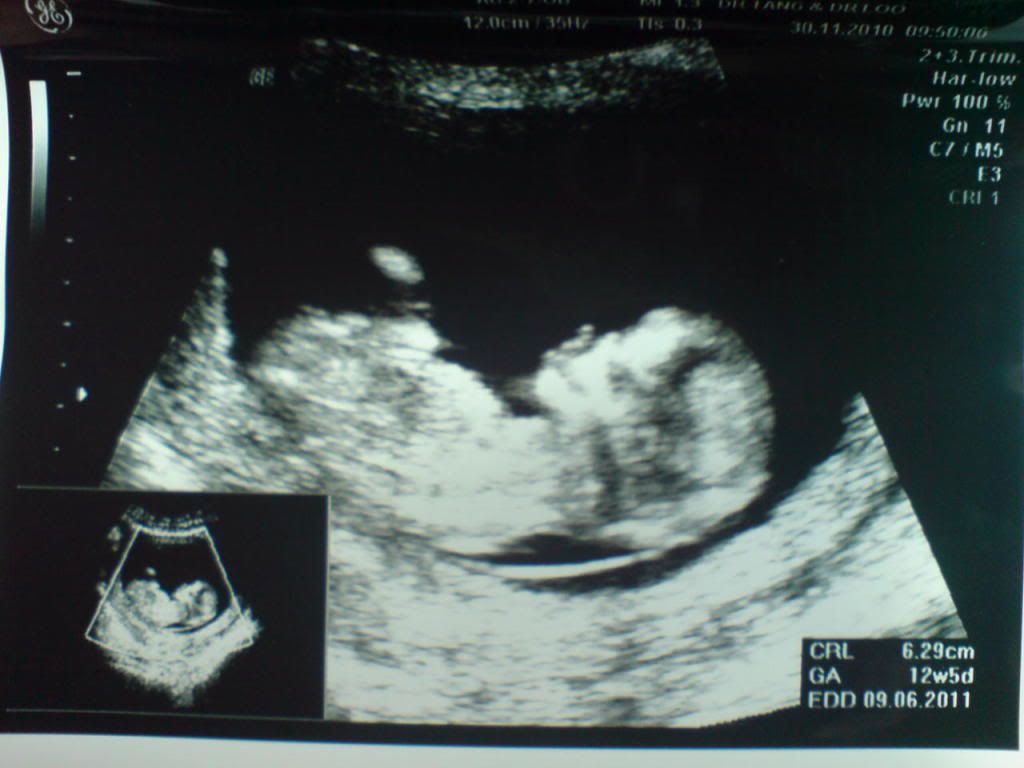

今天来分享第二次产检经过了。

30/11/10是我第二次的产检。

这次产检也是和上回一样是93元。

而体重方面,这次是比上回上升0.1kg。

现在来分享一下宝宝的照片。